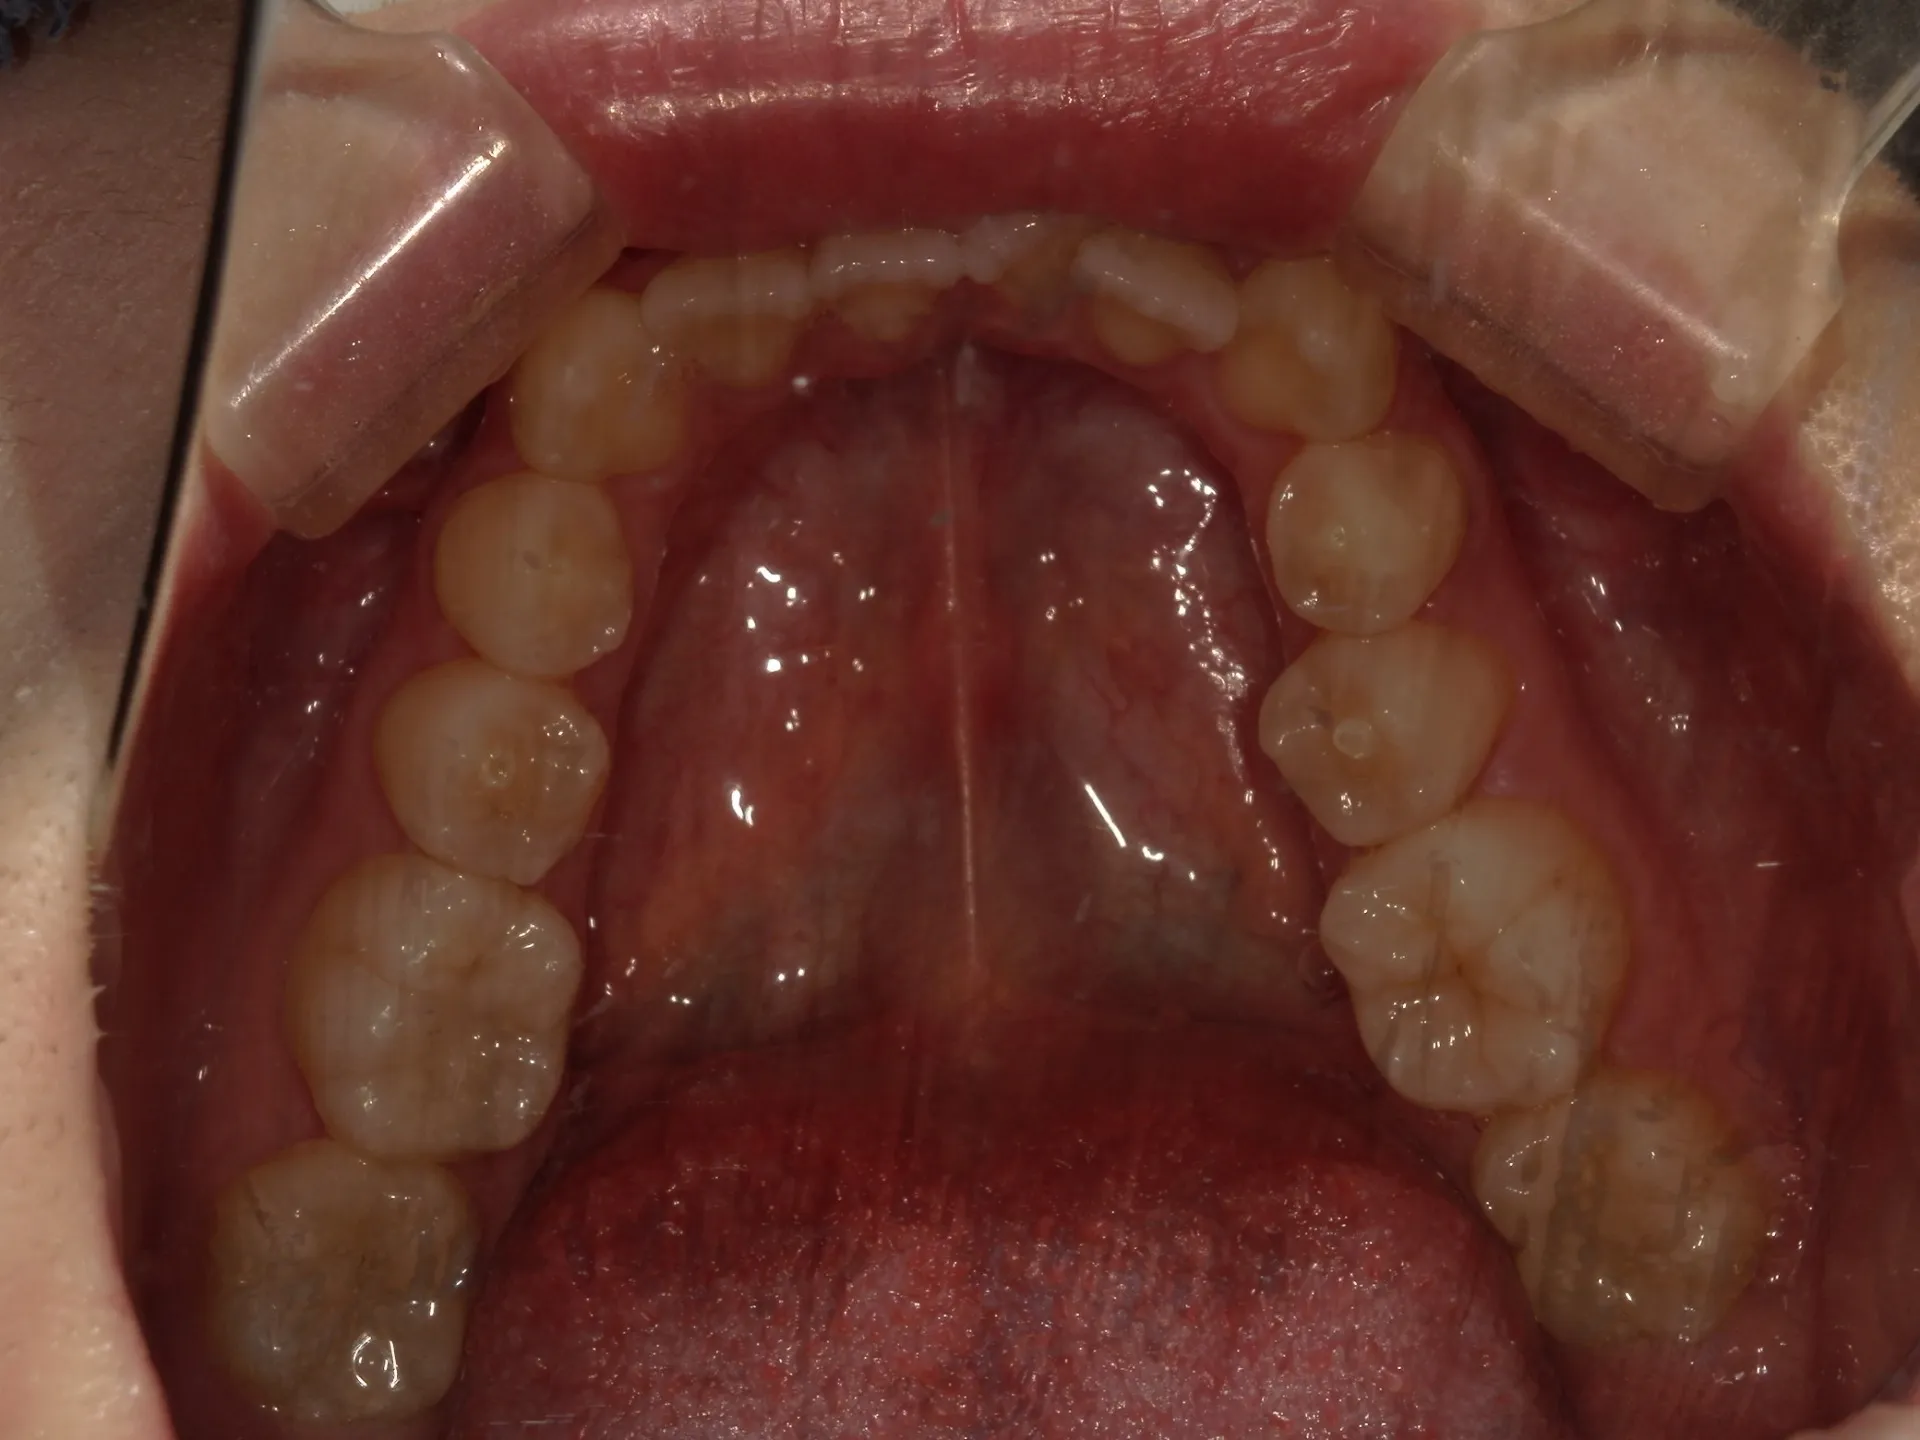

今回はマウスピース矯正で治療した八重歯の矯正についてご紹介いたします。

どこまでが軽度でどこまでが中等度のガタツキなのかにもよりますが、治療前の歯並びであれば患者さんの協力も当然必要ですが、マウスピース矯正でも十分治療できることが分かります。